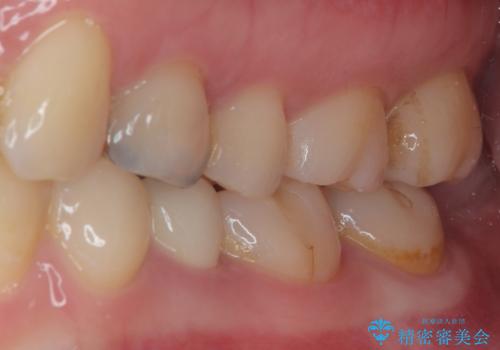

- 左下の被せものが割れたとのことで来院された患者様です。検査の結果、左下の前から4番目の歯はセラミックインレー修復、左下の5番目のところはオールセラミッククラウンによる補綴治療を行っていくことにしました。

拡大鏡視野下で被せもの、虫歯の除去を行い、オールセラミッククラウン、セラミックインレーに適した形に整えました。

歯と歯茎の間に圧排糸と言われる糸を入れてシリコーン印象材にて精密な型どりをしました。

適合の良い被せものが入り、審美面も気に入っていただけました。被せものが割れていたという経緯もあったため少しだけ被せものの厚みを多めに確保してあります。